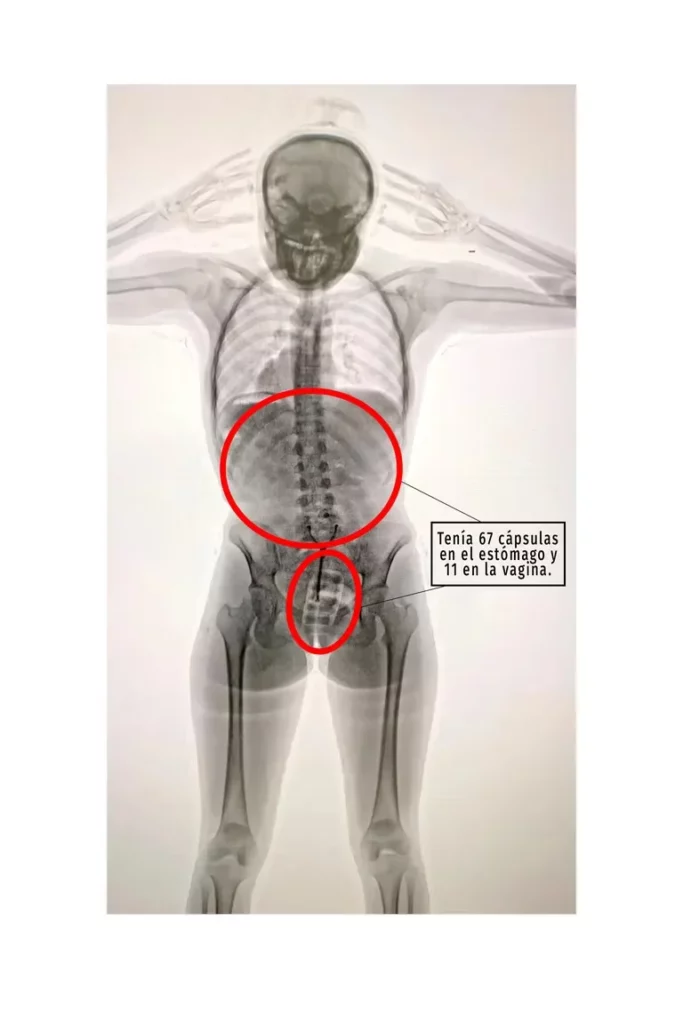

El principal factor que levanta la sospecha de los inspectores de Aduana es que, quienes llevan a cabo este tipo de maniobras, suelen estar dispersas y evasivas, y este fue el caso de la joven. Según trascendió, la pasajera respondió las preguntas que le hicieron “de manera incongruente y dubitativa” y, ante esta situación, la Policía de Seguridad Aeroportuaria (PSA), junto con funcionarios de la Dirección General de Aduanas y personal de AIRCOP, le realizaron un control corporal no invasivo mediante un equipo de rayos X y con presencia de testigos.

El resultado fue la revelación del delito: las imágenes determinaron la presencia de elementos extraños al organismo.

Consecuentemente, -con una orden judicial en mano- la pasajera debió ser requisada hasta que confesó y manifestó que había introducido un profiláctico con once cápsulas de cocaína en su cuerpo, de aproximadamente diez gramos cada una.